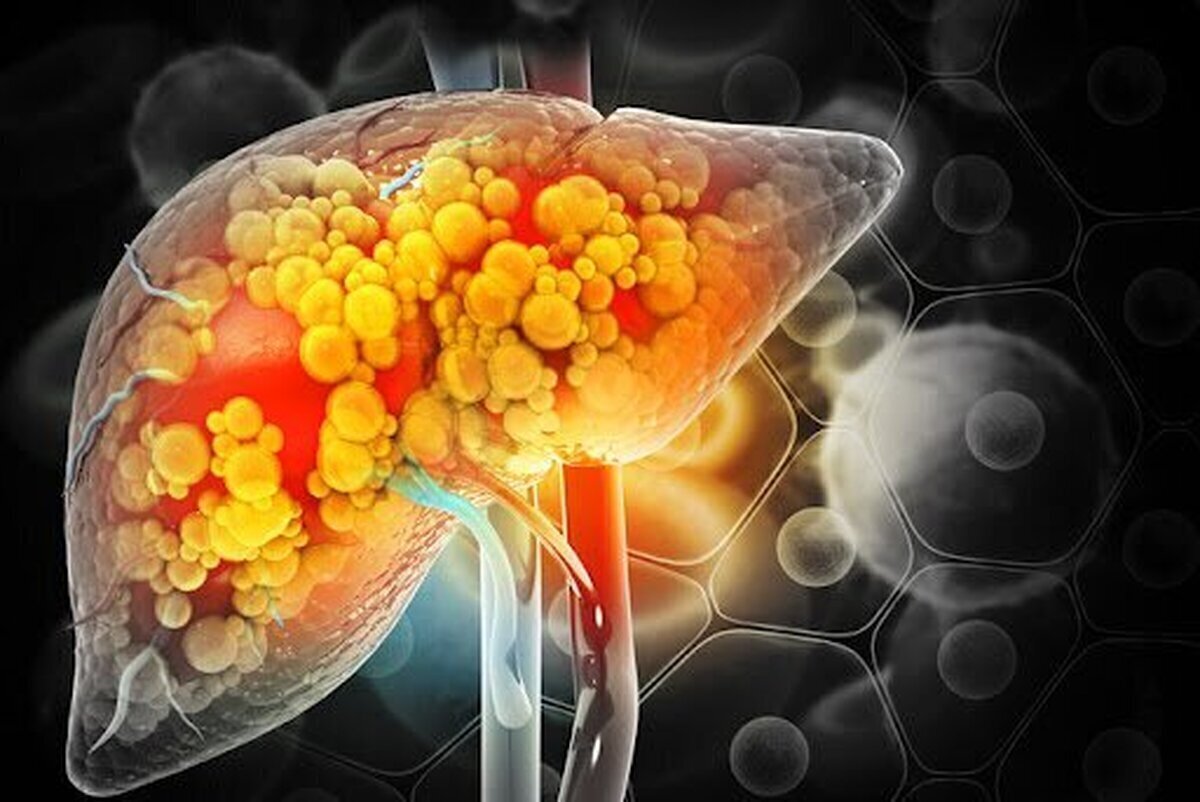

سیدعلی کشاورز، متخصص تغذیه با اشاره به افزایش بیسابقهی کبد چرب در میان جوانان و میانسالان هشدار داد و گفت: کبد چرب بیماری خاموشی است که تا مراحل پیشرفته معمولاً هیچ علامت مشخصی ندارد و متأسفانه زمانی که بروز پیدا میکند، ممکن است وارد مرحلهی خطرناک یا حتی سرطانی شده باشد. اغلب افرادی که به ظاهر مشکلی ندارند، اما سبک تغذیهای ناسالم دارند، در معرض ابتلاء به این بیماری قرار دارند.

وی با اشاره به عوامل ایجاد کبد چرب، گفت: مهمترین عامل مصرف مشروبات الکلی است. پس از آن، مصرف مداوم فستفودها، گوشتهای پرچرب مانند گردن، شیشلیک و ماهیچههای بازاری، غذاهای سرخشده مانند کتلت و کوکو، تهدیگ، شیرینیجات صنعتی مثل کیک، بیسکویت، کلوچه، شکلات، تخمه و آجیل شور و پرچرب، قند و شکر، نوشابه، شربتهای شیرین و غذاهای فرآوریشده از عوامل جدی بروز این بیماری هستند.

وی خاطر نشان کرد: درمان کبد چرب در وهله اول با اصلاح تغذیه آغاز میشود. افرادی که حتی گرید ۲ یا ۳ این بیماری را دارند، بهتر است از مصرف گوشت قرمز پرهیز کرده و میزان روغن مصرفی را به شدت کاهش دهند. گوشت سفید مانند مرغ و ماهی باید به صورت آبپز، بخارپز یا هوا پز تهیه شود. همچنین مصرف سبزیجات پخته، سالاد بدون سس و سبزی خوردن پیش از غذا توصیه میشود. حبوبات مانند عدسی و ماش نیز در پاکسازی کبد بسیار مؤثر هستند.

کشاورز در پایان با تأکید بر قابلبرگشت بودن کبد چرب در مراحل اولیه، گفت: اگر فرد در زمان مناسب نسبت به اصلاح عادتهای غذایی خود اقدام کند، کبد میتواند خود را بازسازی کرده و به وضعیت طبیعی بازگردد. اما در صورت بیتوجهی، خطر ابتلاء به بیماریهای مزمن و حتی سرطان کبد وجود دارد.